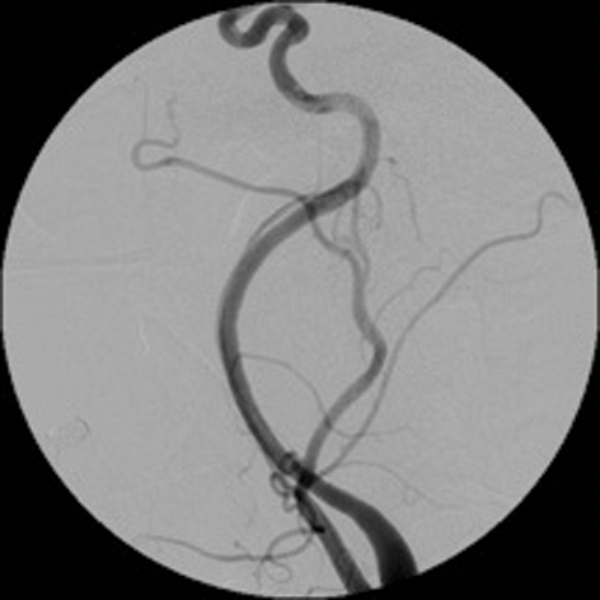

Embolisation is also effective in paragangliomas (glomus tympanicum, glomus jugulare and carotid body tumours). These are tumours arising from paraganglionic chemoreceptor cells which receive their blood supply from the ascending pharyngeal artery. They can be multicentric, locally invasive with malignant potential. Preoperative embolisation of paragangliomas greatly facilitates surgery and reduces the operative time and reduces the associated morbidity [3, 4]. (Figure 2 shows a case of preoperative embolisation of a glomus vagale tumour).

Figure 2: Glomus vagale before and after embolisation.